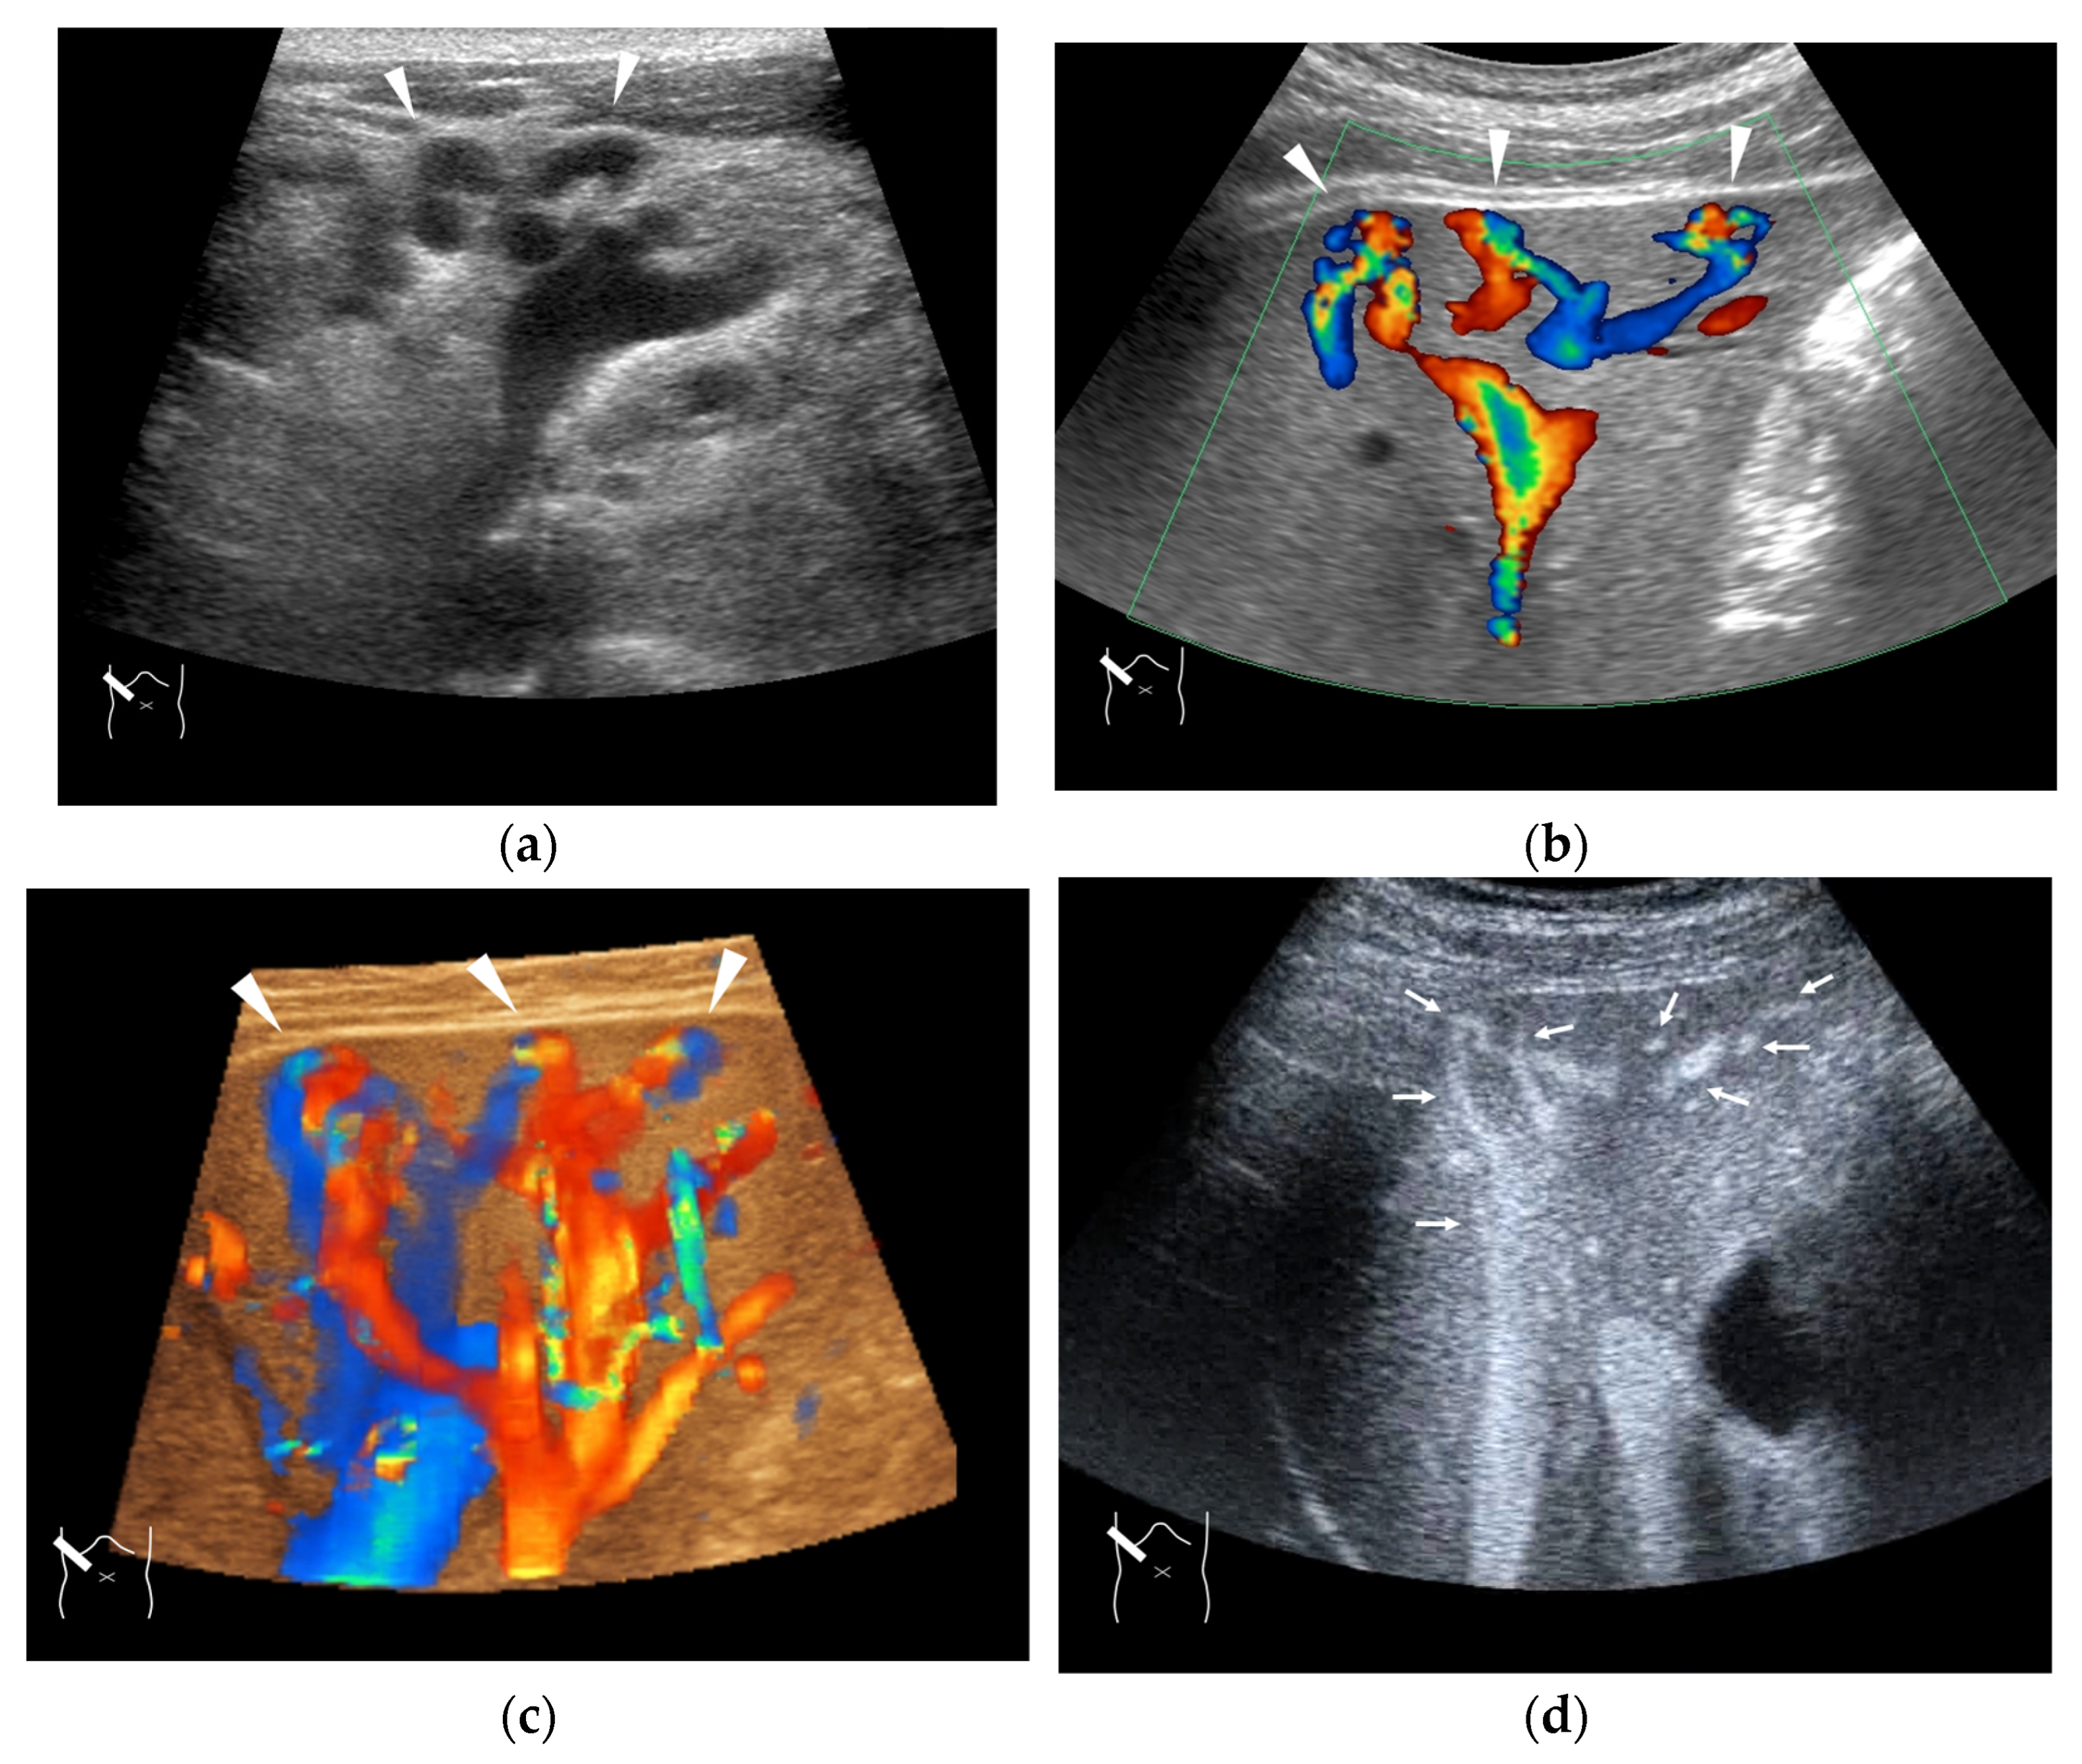

Figure 4.

Representative case of surgically resected well-differentiated HCC arising from minimally fibrotic (F1) liver: (a) B-mode reveals HCC in segment 6 (arrow heads). (b,c) Color Doppler shows tumor vascularities in a basket pattern (arrow heads) and a hepatic vein (arrows). (d) CEUS reveals a markedly enhanced HCC lesion (arrow heads). A hepatic vein (arrows) is enhanced immediately after tumor enhancement.